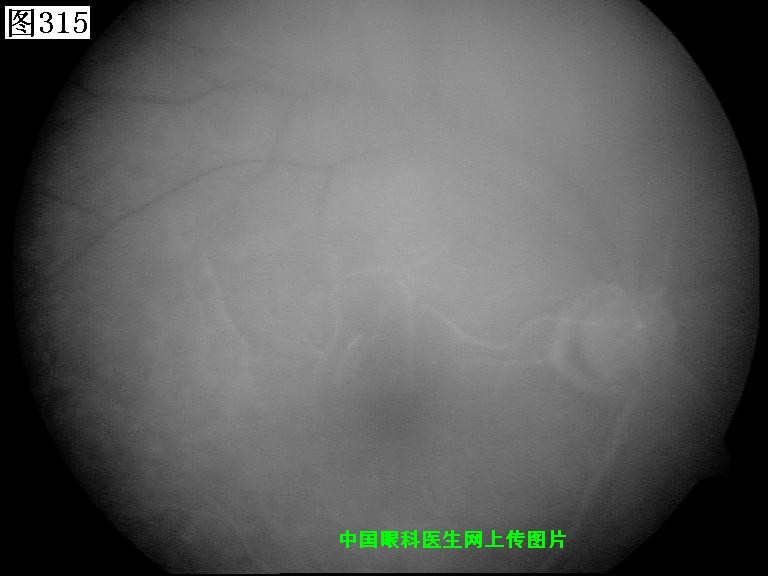

313 314 315 316